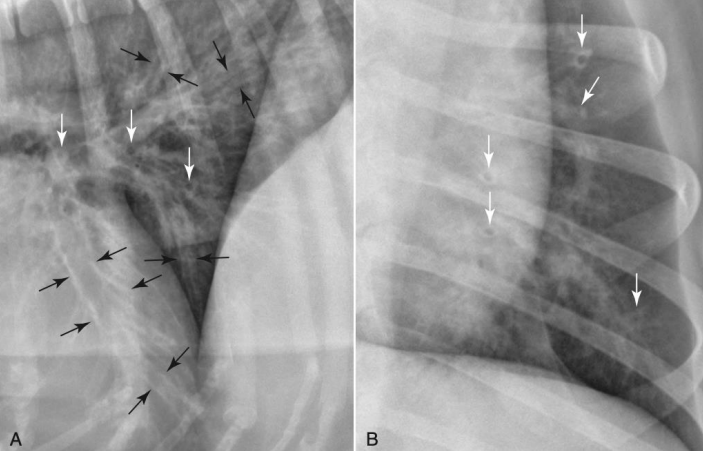

dpseh voxjs?

ํ˜ˆ๊ด€๊ณผ ์ด์–ด์ ธ ํฐ์ƒ‰ ์ ์œผ๋กœ ๋ณด์ด๋Š” ํŒจํ„ด

ํ˜ˆ๊ด€์ด ์—†๋Š”๋ฐ ๋œฌ๊ธˆ์—†์ด ์žˆ๋Š” ํฐ ์ ? ์ „์ด๋œ ์ข…์–‘

๋ง๋‹จ์—๋Š” ํฐ ํ˜ˆ๊ด€์ด ์—†์œผ๋‹ˆ๊นŒ ์—”๋ˆ ํŒจํ„ด์ด ์ƒ๊ธธ ์ˆ˜ ์—†๋‹ค

๊ธฐ๊ด€์ง€๊ฐ€ ์—„์ฒญ ๋„“์„ ๋•Œ bronchiectasis

Lobar sign

alverolar pattern์ด ํ•œ ์—ฝ์—๋งŒ ์ง„ํ•˜๊ณ  ๋šœ๋ ทํ•˜๊ฒŒ ๋‚˜ํƒ€๋‚ฌ์„ ๋•Œ.

ํฐ์ƒ‰ ๋ถ€๋ถ„์— alveolar pattern ๋šœ๋ ท